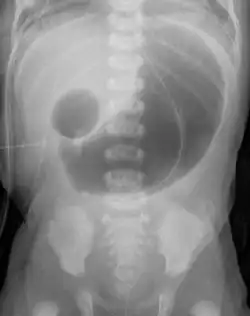

Das gleiche Phänomen kann auch nach der Geburt durch eine Röntgenuntersuchung gesehen werden. Dadurch, dass sich der obere Magen-Darm-Trakt nach der Geburt mit Luft füllt, entsteht eine Luftblase im Magen, sowie eine im Duodenum. Der übrige Darmtrakt ist luftleer.